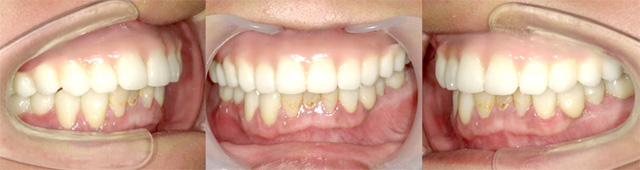

当院で治療された方の症例集をご覧ください!

オールオン4の治療例:1

治療前

治療後

オールオン4の治療例:2

その他 ボロボロ虫歯の症例